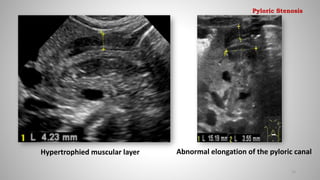

Pyloric Stenosis

Ultrasonography

• Primary imaging method

• Sensitivity and specificity of approximately 100%

• USG confirmed hypertrophic pyloric stenosis when:

- pyloric muscle thickness (MT) > 4 mm &

- pyloric channel length (CL) > 15 mm

But,

• Linear relationship between Pyloric MT, CL Vs Patient age

• 3 mm MT (diagnostic for pyloric stenosis in younger patients)

Hypertrophied muscular layer Abnormal elongation of the pyloric canal